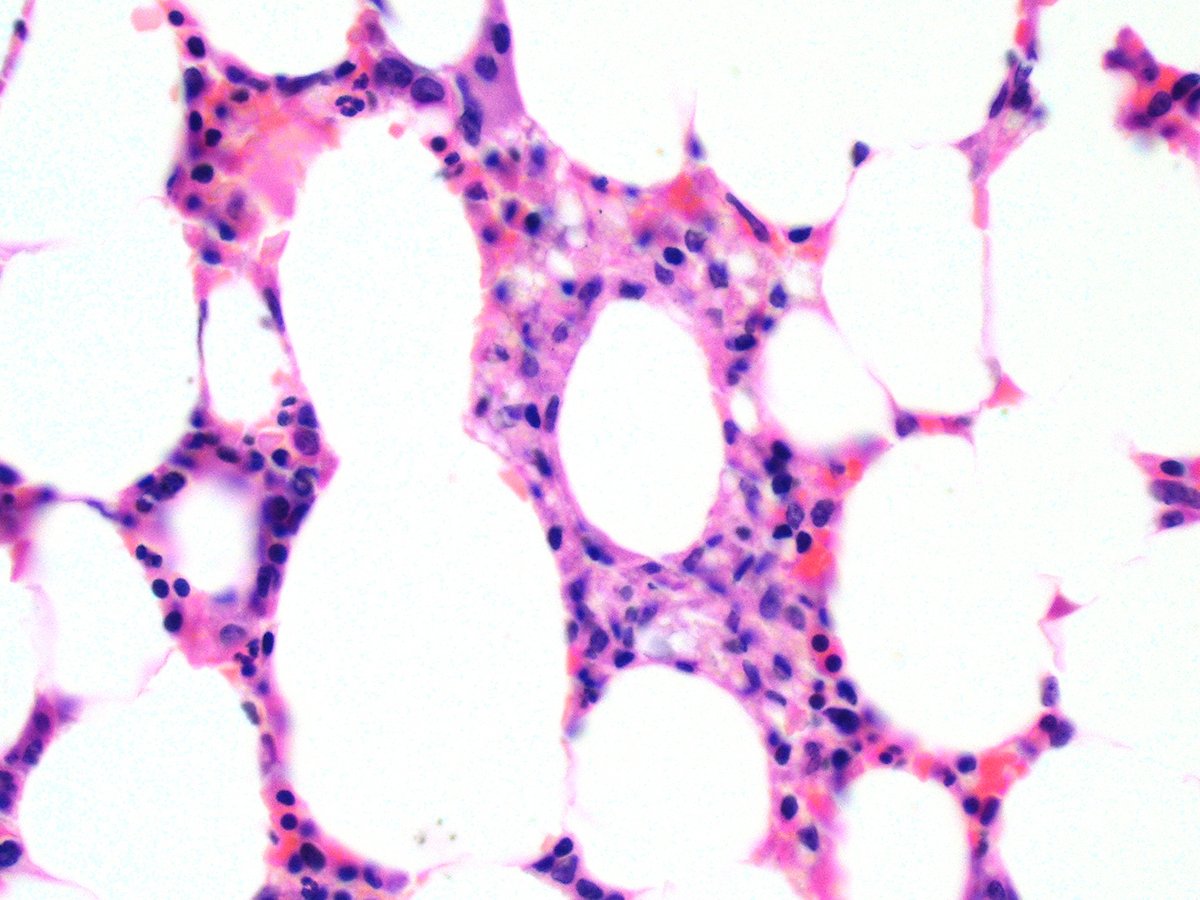

@KukMariya Myelolipomas are clonal. I published this a million years ago.

Hey Pathology twitter! Thoughts?